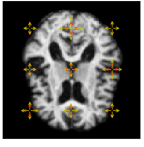

Refer to caption

Figure 2: First row: (left) The noise fields location on the domain. (middle) Initial brain, I0subscript𝐼0I_{0}. (right) Variation in the data sample. Second row: 3 examples of simulated data by the stochastic deformation ϕt1superscriptsubscriptitalic-ϕ𝑡1\phi_{t}^{-1}.

By drawing sample paths of the stochastic flow ϕt1superscriptsubscriptitalic-ϕ𝑡1\phi_{t}^{-1}, we obtain samples of deformed images under the model. Sample images at t=1𝑡1t=1 are shown in Fig. 2, together with a plot of the generated image variation, and the noise fields used to simulate the sample data. Fig. 3 shows 4 time points from a sample path of the stochastic process I0ϕt1subscript𝐼0superscriptsubscriptitalic-ϕ𝑡1I_{0}\circ\phi_{t}^{-1} for t=0, 0.25, 0.5, 1𝑡00.250.51t=0,\,0.25,\,0.5,\,1.

The first data sample was simulated based on 9 Gaussian noise fields. The location of the noise fields is shown in Fig. 2, which also shows the initial brain image, I0subscript𝐼0I_{0}. The variation of the simulated data sample is visualized in Fig. 4.